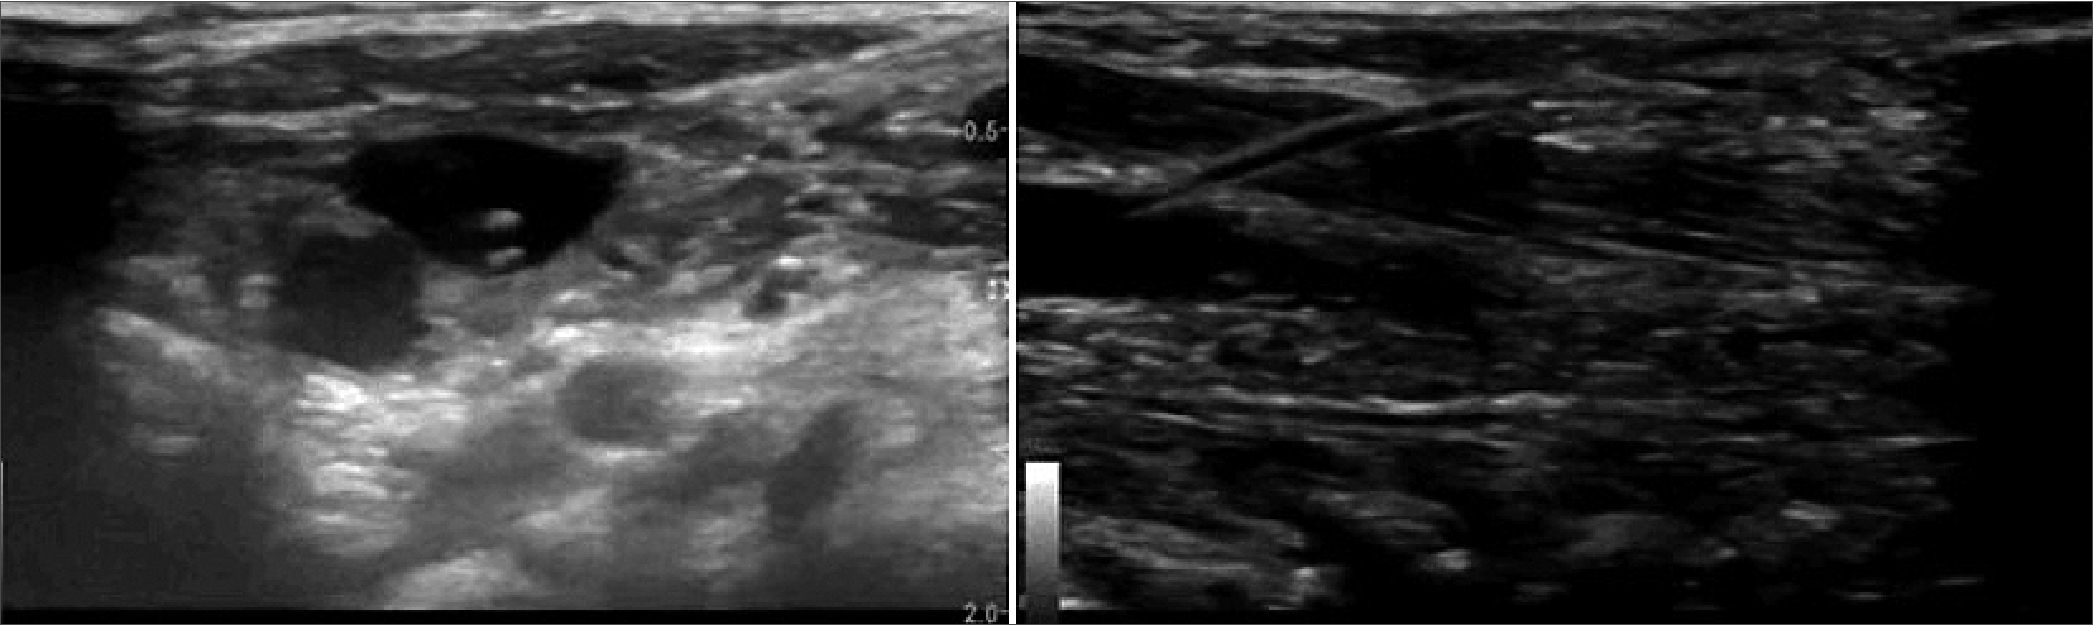

Paciente de femenina de 3 meses, 4 kg de peso, con diagnóstico de shock séptico y Síndrome de Distrés Respiratorio Agudo Pediátrico (SDRAP) grave, por neumonía de la comunidad. A su ingreso al hospital requiere ventilación invasiva y se coloca CVC subclavio derecho para terapéutica y monitoreo. El día 3 se coloca en posición prono para optimizar oxigenación, logrando objetivos. El día 4, el catéter muestra signos de obstrucción mecánica, que no logra solucionarse y se coloca al paciente en supino para realizar un nuevo CVC, presentando caída de oxigenación, y se reposiciona en prono, recuperándose. POCUS de la región cervical dorsolateral bilateral con transductor lineal de 10 MHz y 4 cm de ancho, en posición axial, muestra las venas yugulares internas (VYI) izquierda de 4 mm y derecha de 5 mm de diámetro en su eje menor, ambas a 9 mm de profundidad (Figura 1). Puncionamos fuera de plano derecho, con búsqueda dinámica de la punta de la aguja a 45°, encontrando la vena a la primera punción, introduciendo guía flexible y luego catéter 4 Fr trilumen, fijado en 7 cm a piel en región dorsal superior del tórax (Figura 2). El día 6 la paciente cumple con criterios para colocarse en decúbito supino, cambiando sentido de la fijación externa del catéter hacia región anterior del tórax del paciente. Continua con evolución satisfactoria, hasta extubarse en el día 11 de tratamiento. El catéter continuó funcional y se retira en el día 16 para continuar farmacoterapia por acceso vascular periférico.

Figura 1.